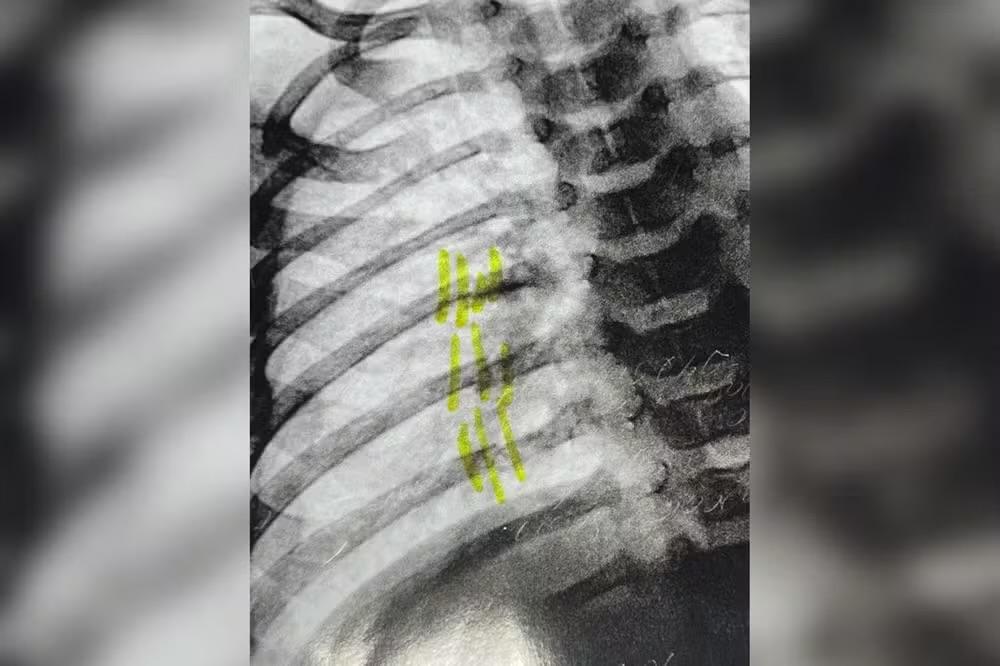

De acordo com informações apuradas pela TV TEM, o bebê apresentava ferimentos no pescoço e três costelas quebradas. A equipe da UPA acionou o Conselho Tutelar, que, com o apoio da Guarda Municipal, deteve o homem e levou a mãe do bebê, de 26 anos, para a delegacia.